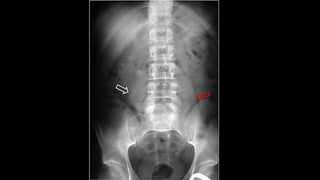

SIGNO DE LA LÍNEA DEL PSOAS

• Utilizado en el diagnóstico diferencial de la patología

intraabdominal y la retroperitoneal.

• El borramiento de la línea del psoas sucede en procesos con

alteración de la radiotransparencia de la grasa

retroperitoneal(infiltración por sangre, edema, líquido o

tumoración).

• La línea del psoas puede no verse en hasta un 40 % de sujetos

normales y puede estar conservada la línea en presencia de

patología retroperitoneal, por lo que su utilidad es muy escasa.

SIGNO DE LALÍNEA DEL PSOAS • Utilizado en el diagnóstico diferencial de la patología intraabdominal y la retroperitoneal. • El borramiento de la línea del psoas sucede en procesos con alteración de la radiotransparencia de la grasa retroperitoneal(infiltración por sangre, edema, líquido o tumoración). • La línea del psoas puede no verse en hasta un 40 % de sujetos normales y puede estar conservada la línea en presencia de patología retroperitoneal, por lo que su utilidad es muy escasa.